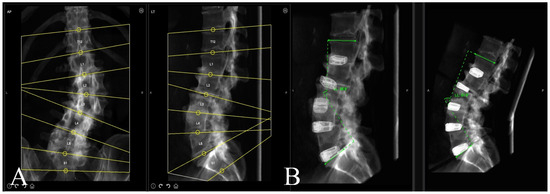

A preoperative thin-cut CT scan is obtained and loaded into the planning software associated with the spinal robotics system (Mazor X Robotics Planning Software Version 5.0 with X-Align, Medtronic Sofamor Danek, Minneapolis, MN, USA) (Figure 1A). Interbody cages are then planned and simulated. Of note, the software assumes full movement of the chosen segment based on cage geometry and marked endplate surfaces, and under-correction of the simulation may oftentimes be needed due to rigid deformities or facet ankylosis and hypertrophy (Figure 1B and Figure 2). With this correction provided, pedicle and iliac screws are then planned from the UIV to S2 and bilateral rods are simulated after each screw to confirm appropriate planar alignment (Figure 3). Adjustments to the trajectories of the pedicle screws can be made to ensure easy subfascial passage. Satellite accessory rods are planned using lateral-to-medial screw trajectories with positions outside of the main rod. While open surgical techniques allow for satellite rod placement with dual-headed screws or rod–rod domino connectors, the lack of direct visualization in MIS makes these strategies prohibitive and therefore satellite rods are usually not able to be directly connected to the main rod (Figure 4).

Figure 2. Coronal simulation of interbody cage placement to assess if minimally invasive placement of interbodies can effectively correct fractional and main coronal curve deformities through movement at each vertebral segment.